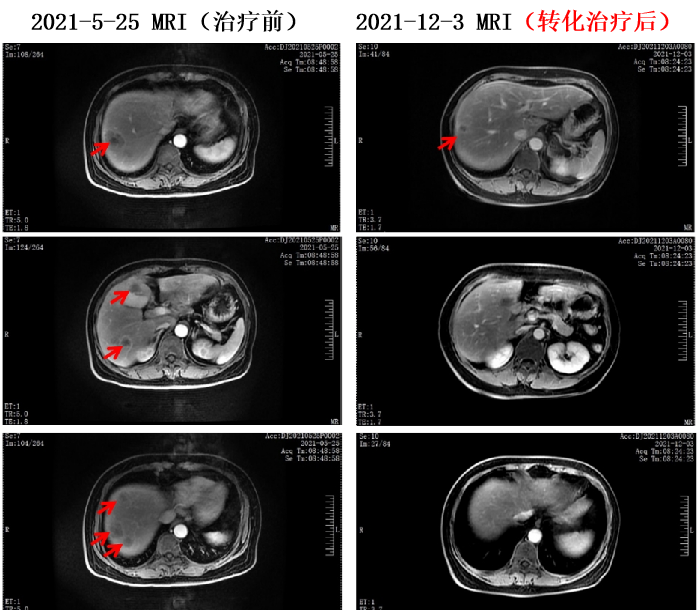

2021-5-29至2021-9-21 共行6周期 贝伐珠单抗+伊立替康+奥沙利铂+卡培他滨方案化疗。

疗效评价为PR,经外科评估可行手术治疗,遂术前停用贝伐珠单抗。

为不降低治疗强度,将卡培他滨调整为雷替曲塞。

2021-10-16至2021-11-9 行2周期 伊立替康+奥沙利铂+雷替曲塞方案化疗。